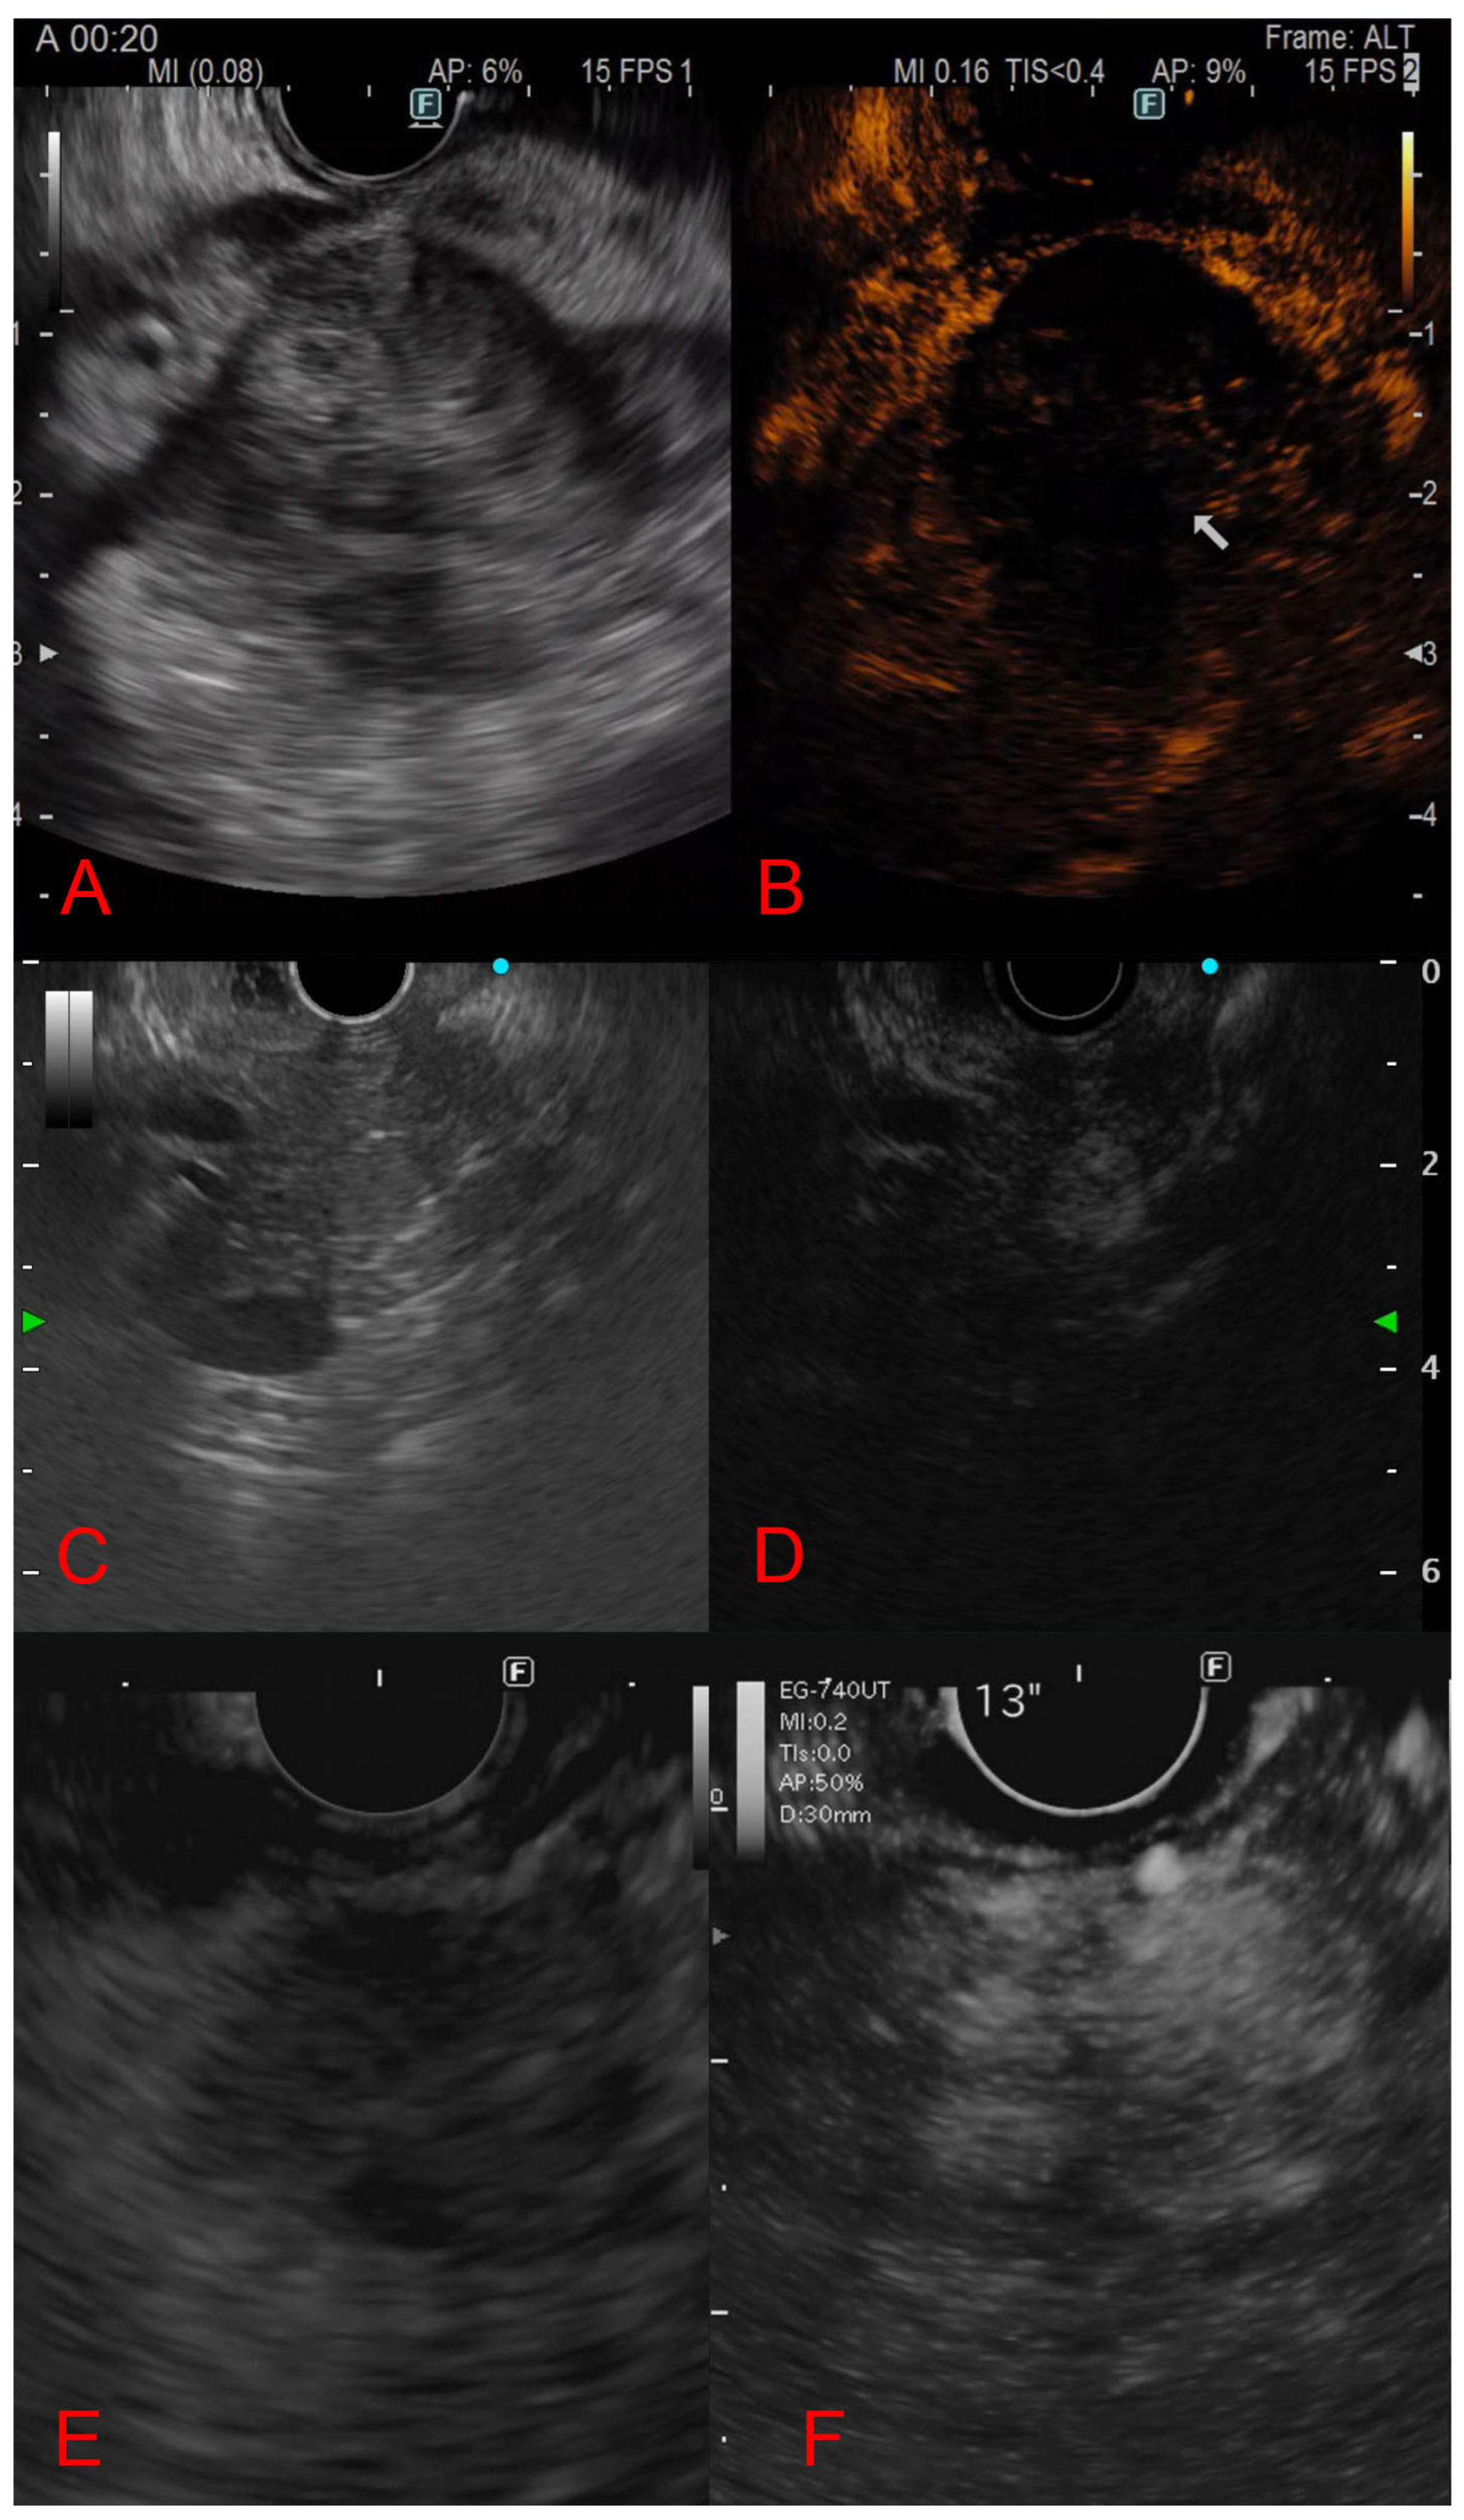

3.5. Contrast-Enhanced Endoscopic Ultrasound Features

| CE-EUS pattern | Hyper-/hypoenhancing | Hypoenhancing | Hyperenhancing | Hyper-/isoenhancing |